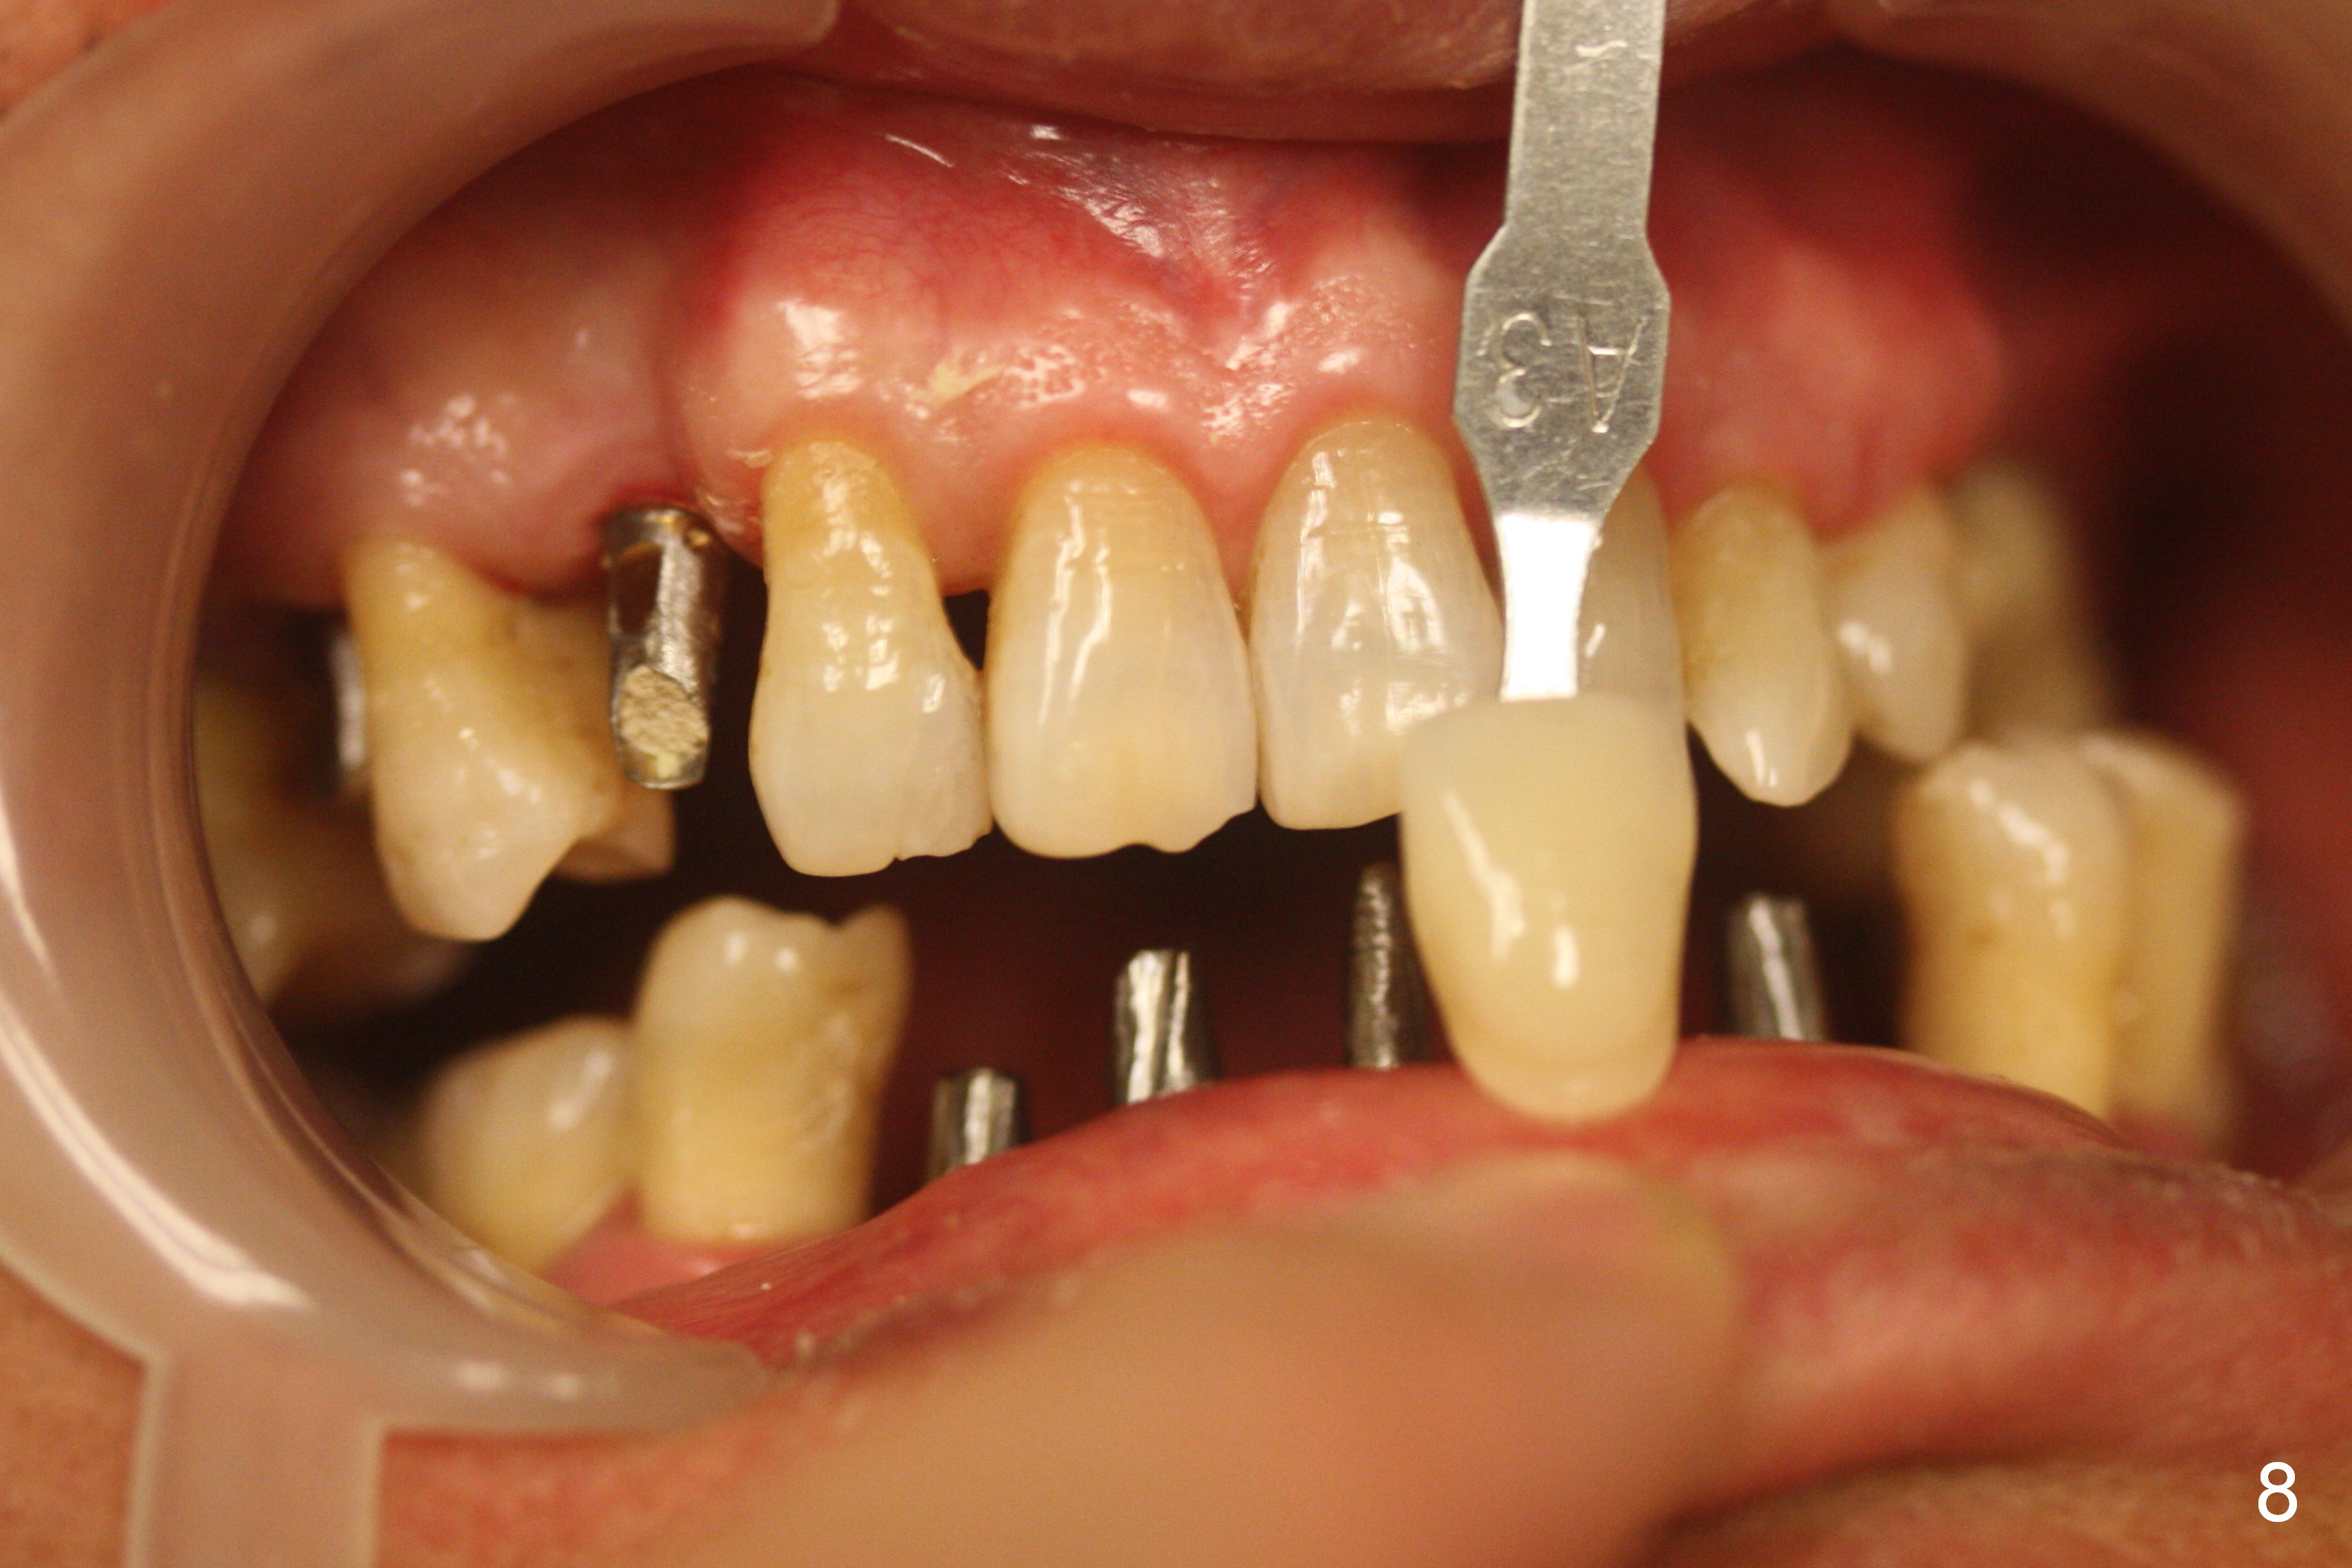

The patient returns for restoration 4.5 months postop (Fig.7-9). There appears bone growth around the implants. Impression is taken together with the implants at #4 and 6.

When the final crowns are seated, the shade is off. It appears that C3 is appropriate (Fig.10,11). Please make the crowns more transparent.